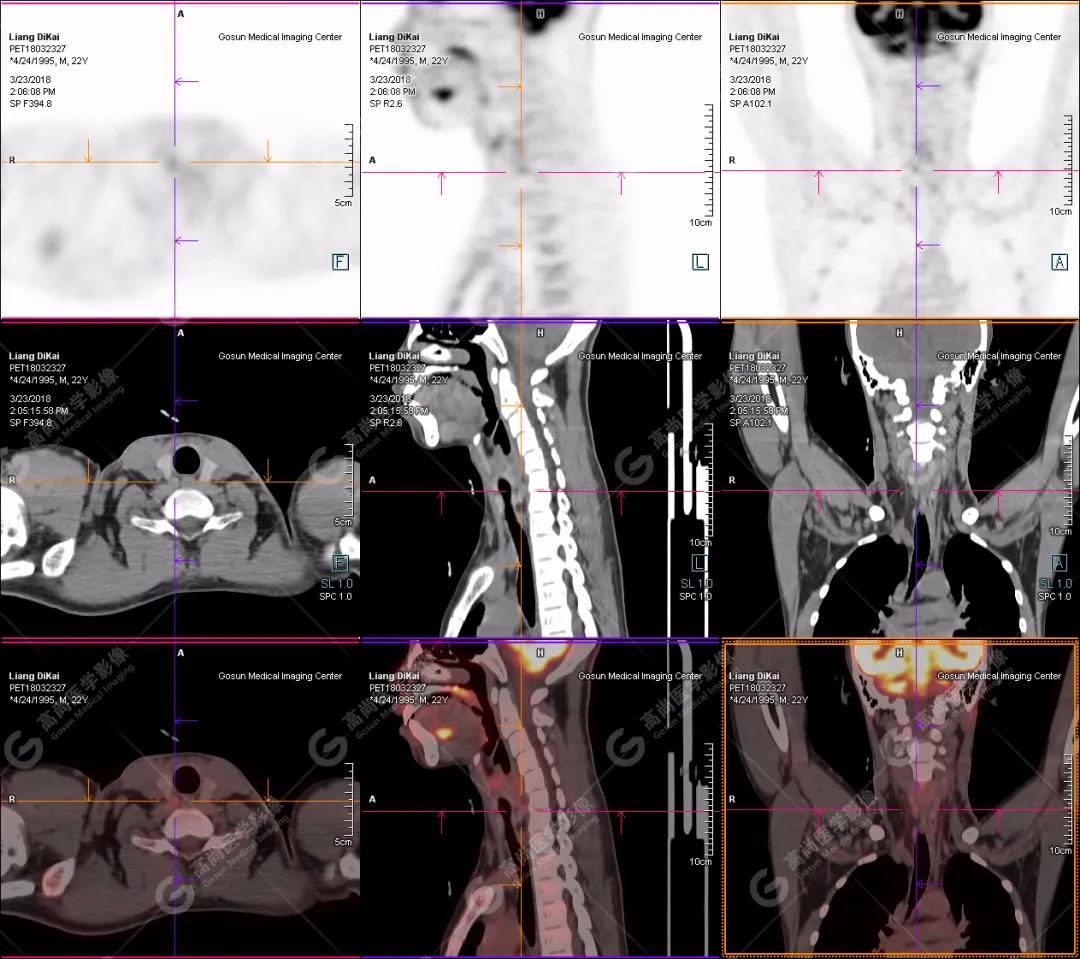

【廣東高尚醫(yī)學(xué)影像病例】PET/CT在副腫瘤綜合征尋找原發(fā)灶應(yīng)用

男性,23歲,反復(fù)血鈣升高1年;左側(cè)臀部、右肘部腫物進(jìn)行性生長2年。既往2017年尿毒癥腎移植術(shù)后;鈣磷代謝異常。否認(rèn)結(jié)核、乙肝等其它手術(shù)史。

本中心PET/CT提示

1.右肘關(guān)節(jié)周圍、骶尾部皮下、雙側(cè)臀部、盆腔左側(cè)壁及左側(cè)大腿根部肌肉、肌間隙多發(fā)結(jié)節(jié)狀、片塊狀及不規(guī)則巨塊狀高密度鈣化灶,伴代謝不均勻輕度增高,考慮為鈣質(zhì)沉著癥;

2.甲狀腺雙葉后方多發(fā)(右2個,左1個)小結(jié)節(jié)狀軟組織影,部分代謝輕度增高,多考慮為甲狀旁腺腺瘤。

患者行甲狀腺雙葉后方結(jié)節(jié)切除,術(shù)后病理甲狀旁腺腺瘤;病灶切除后,全身多發(fā)腫塊逐漸消失。